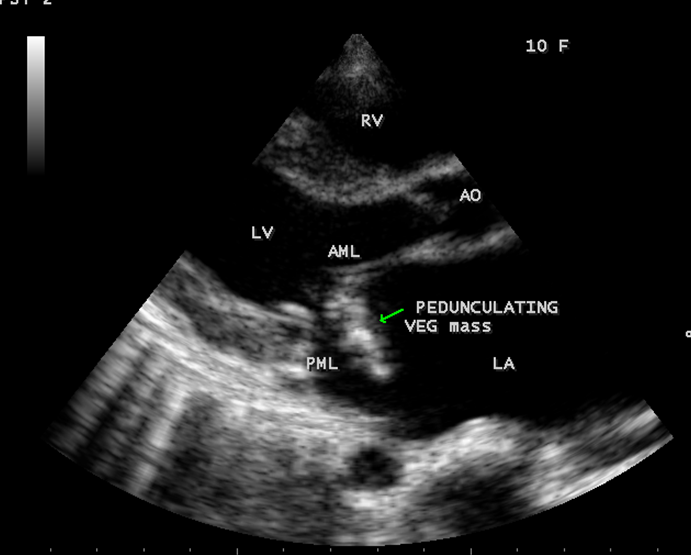

Echocardiography is the only noninvasive method available for direct visualization of endocarditis-induced lesions. Echocardiographic finding in patients with infective endocarditis was initially observed by Dillon [25] and Spangler, et al [26]. The vegetation will grow in size, either as a sessile clump or a highly mobile and even pedunculated mass with the potential for embolization. Vegetation can be detected when the valve attached mass reach a diameter of ≥ 2 to 3 mm [27]. In both children and adults, 2-D echocardiography is usually the more sensitive technique with sensitivity in children up to 80% [28]. Valvular dysfunction due to tissue disruption or large obstructing vegetation can be visualized and quantitated by echocardiogram with Doppler [29]. The detection of a large eccentric jet adhering, swirling, and reaching the posterior wall of the LA is in favour of significant MR (mitral regurgitation) as shown in Figures 22, 24 and 25.

The most common and direct evidence of infective endocarditis is the vegetation and it begins as a microscopic focus of infection and gradually grows into a conspicuous mass. It is typically an irregularly shaped, highly mobile, echogenic mass attached to the free edge of a valve leaflet ( most commonly at the coaptation line) and tends to develop on the ‘upstream’ side of the valve leaflets ( ie, the ventricular side of aortic valve and the atrial side of mitral and tricuspid valves. They may be seesile or pedunculated, but usually has an oscillating or fluttering motion, a typical feature of most vegetations. Vegetation move with the leaflet in a more chaotic (‘oscillating’) manner and it may prolapse through the valve into the LV (left ventricle) as it opens as shown in Figures 3, 4 and 16 and into LA (left atrium) as it closing (Figure 5 and 6) . The mass of vegetation is typically homogeneous with echogenicity similar to that of the myocardium. The infectious process often alter the valvular structure and function. Extensive involvement of the leaflet may result in chordal rupture, leading to severe regurgitation as shown in Figure 21 . Direct and typical signs of RMCT (ruptured mitral chordate tendineae) were chain-flail or whiplash-like changes and had an incidence of 86.7%, causing severe regurgitation and mitral chordal rupture is the leading cause of flail mitral leaflet[30]. A large vegetation may obstruct the valve orifice as shown in Figure 1 and 2 , sometimes termed as “obstructive-type bacterial endocarditis” and producing a functional valve stenosis ( Ping-Pong mitral stenosis [31]) similar to left atrial myxoma as shown in Figure 29.

The shape and size of vegetation are quite variable and mostly it is polypoid [32]. The typical vegetation is a ‘sessile’ or ‘ pedunculating’ valve – attached mass. A ‘sessile’ vegetation had to be completely attached to the valve as shown in Figures 34 and 35 in a 63- year old male, in which a large vegetation is attached to the atrial side of anterior mitral leaflet [33-Figure 13.3-A], producing severe mitral regurgitation as shown in Figure 36 and a mobile vegetation showed a pedunculating part prolapsing into the ventricle as shown in Figure 3 and 4 or atrium as shown in Figure 5 [33-Figure 13.1] in a 10-year old female child. A vegetation was considered as ‘definite’ when shaggy echoes in the M-mode study as shown in Figure 20 . and a corresponding mass without restricted valve motion in the two-dimensional echocardiogram were found as shown in Figure 16 and 30 [33-Figure 13.7]. The vegetation vary in size, often being just a few mm and sometimes reaching to 2-3 cm. A vegetation must be atleast 3 to 6 mm in size to be reliably seen. The mean size of vegetation was 0.6 mm (range 3 to 28) and vegetation > 10 mm in diameter was defined as ‘large’ and those ≤ 10 mm in diameter was defined as ‘small’ and ≥ 15 mm is ‘very large’. Vegetations resulting from fungal infections (candida, aspergillus) are usually much bigger than bacterial vegetations and can be so big to be mistaken for a cardiac tumor. The large vegetations are at increased risk for embolic complications [34], especially on the anterior leaflet of the mitral valve with mobility [35]. A vegetation size of 3.2 x 4.4 cm is called as ‘giant vegetation’ on the mitral valve with a fibrillary appearance of the mass [36- Figure 3] as shown in Figure 1 is an important predictor of embolic phenomena in patients with infective endocarditis causing severe mitral regurgitation as ‘Duck’ shaped jets (Figures 24 and 25 ), disorganized (Figure 21) and sometimes the regurigitant jet splits into two components as one into LA and the second one into LV simultaneously as a bileaflet jets (Figure 10 ) similar to bileaflet structure of AML with vegetation masses (Figure 9 ) . The size of the largest vegetation reported on the mitral valve in the literature in patients with bacterial endocarditis is 7x4 cm[37]. In a study of Nunes, et al[38], vegetation size >13 mm was the only independent predictor of mortality, but some studies [39],[40] did not had an increased embolic risk in patients with vegetation focused only on its presence and size and not on their location. Embolic complications may occur in infective endocarditis(20.6%)and were not more prevalent in the groups with large vegetations [41]. However, Wong, et al [42] found an increased need for surgery in patients with a large vegetation (>10 mm).

The shape of vegetation varies in this child as ‘popcorn’ like (Figures 1,3 and 4 ), rod-shaped (Figure ), basket shaped (Figure 7 )[33-Figure 13.3], ‘baby in hand’ appearance (Figure 18), ‘cucumber shaped (Figure 2 ) and a ‘bunch of plantain’appearance (Figure 33 ), ring shaped (Figure 19 }, bileaflet structure (Figure 9 )with bileaflet MR jet as shown in Figure 10 . and kissing forms (Figure 13 - parasternal long axis view, Figure 14 - apical four chamber view and Figure 15 - short axis view)